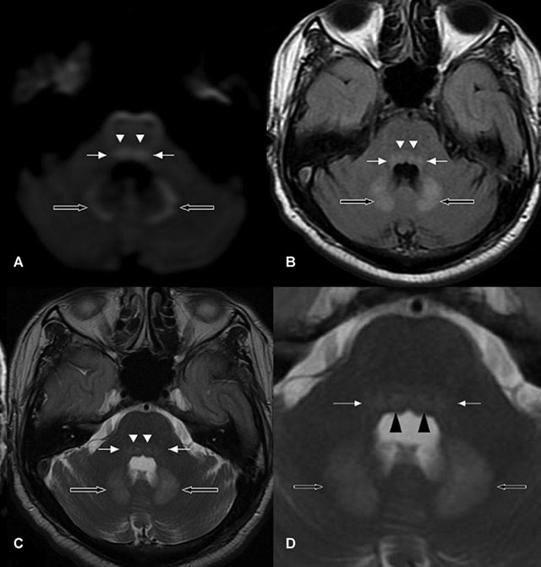

男,58歲,臨床表現(xiàn)為共濟失調、眼震、定向力障礙。SWI提示雙側乳頭體微出血。T1WI增強掃描提示乳頭體強化。

患者表現(xiàn)為意識障礙、肢體不自主運動、小腦性共濟失調、眼球震顫、雙側外直肌麻痹。顱腦MRI示:雙側小腦齒狀核(空箭頭)、前庭神經(jīng)核(白色箭頭)、展神經(jīng)核異常信號(短箭頭);中腦頂蓋、雙側黑質及乳頭體對稱性異常信號。

病例9